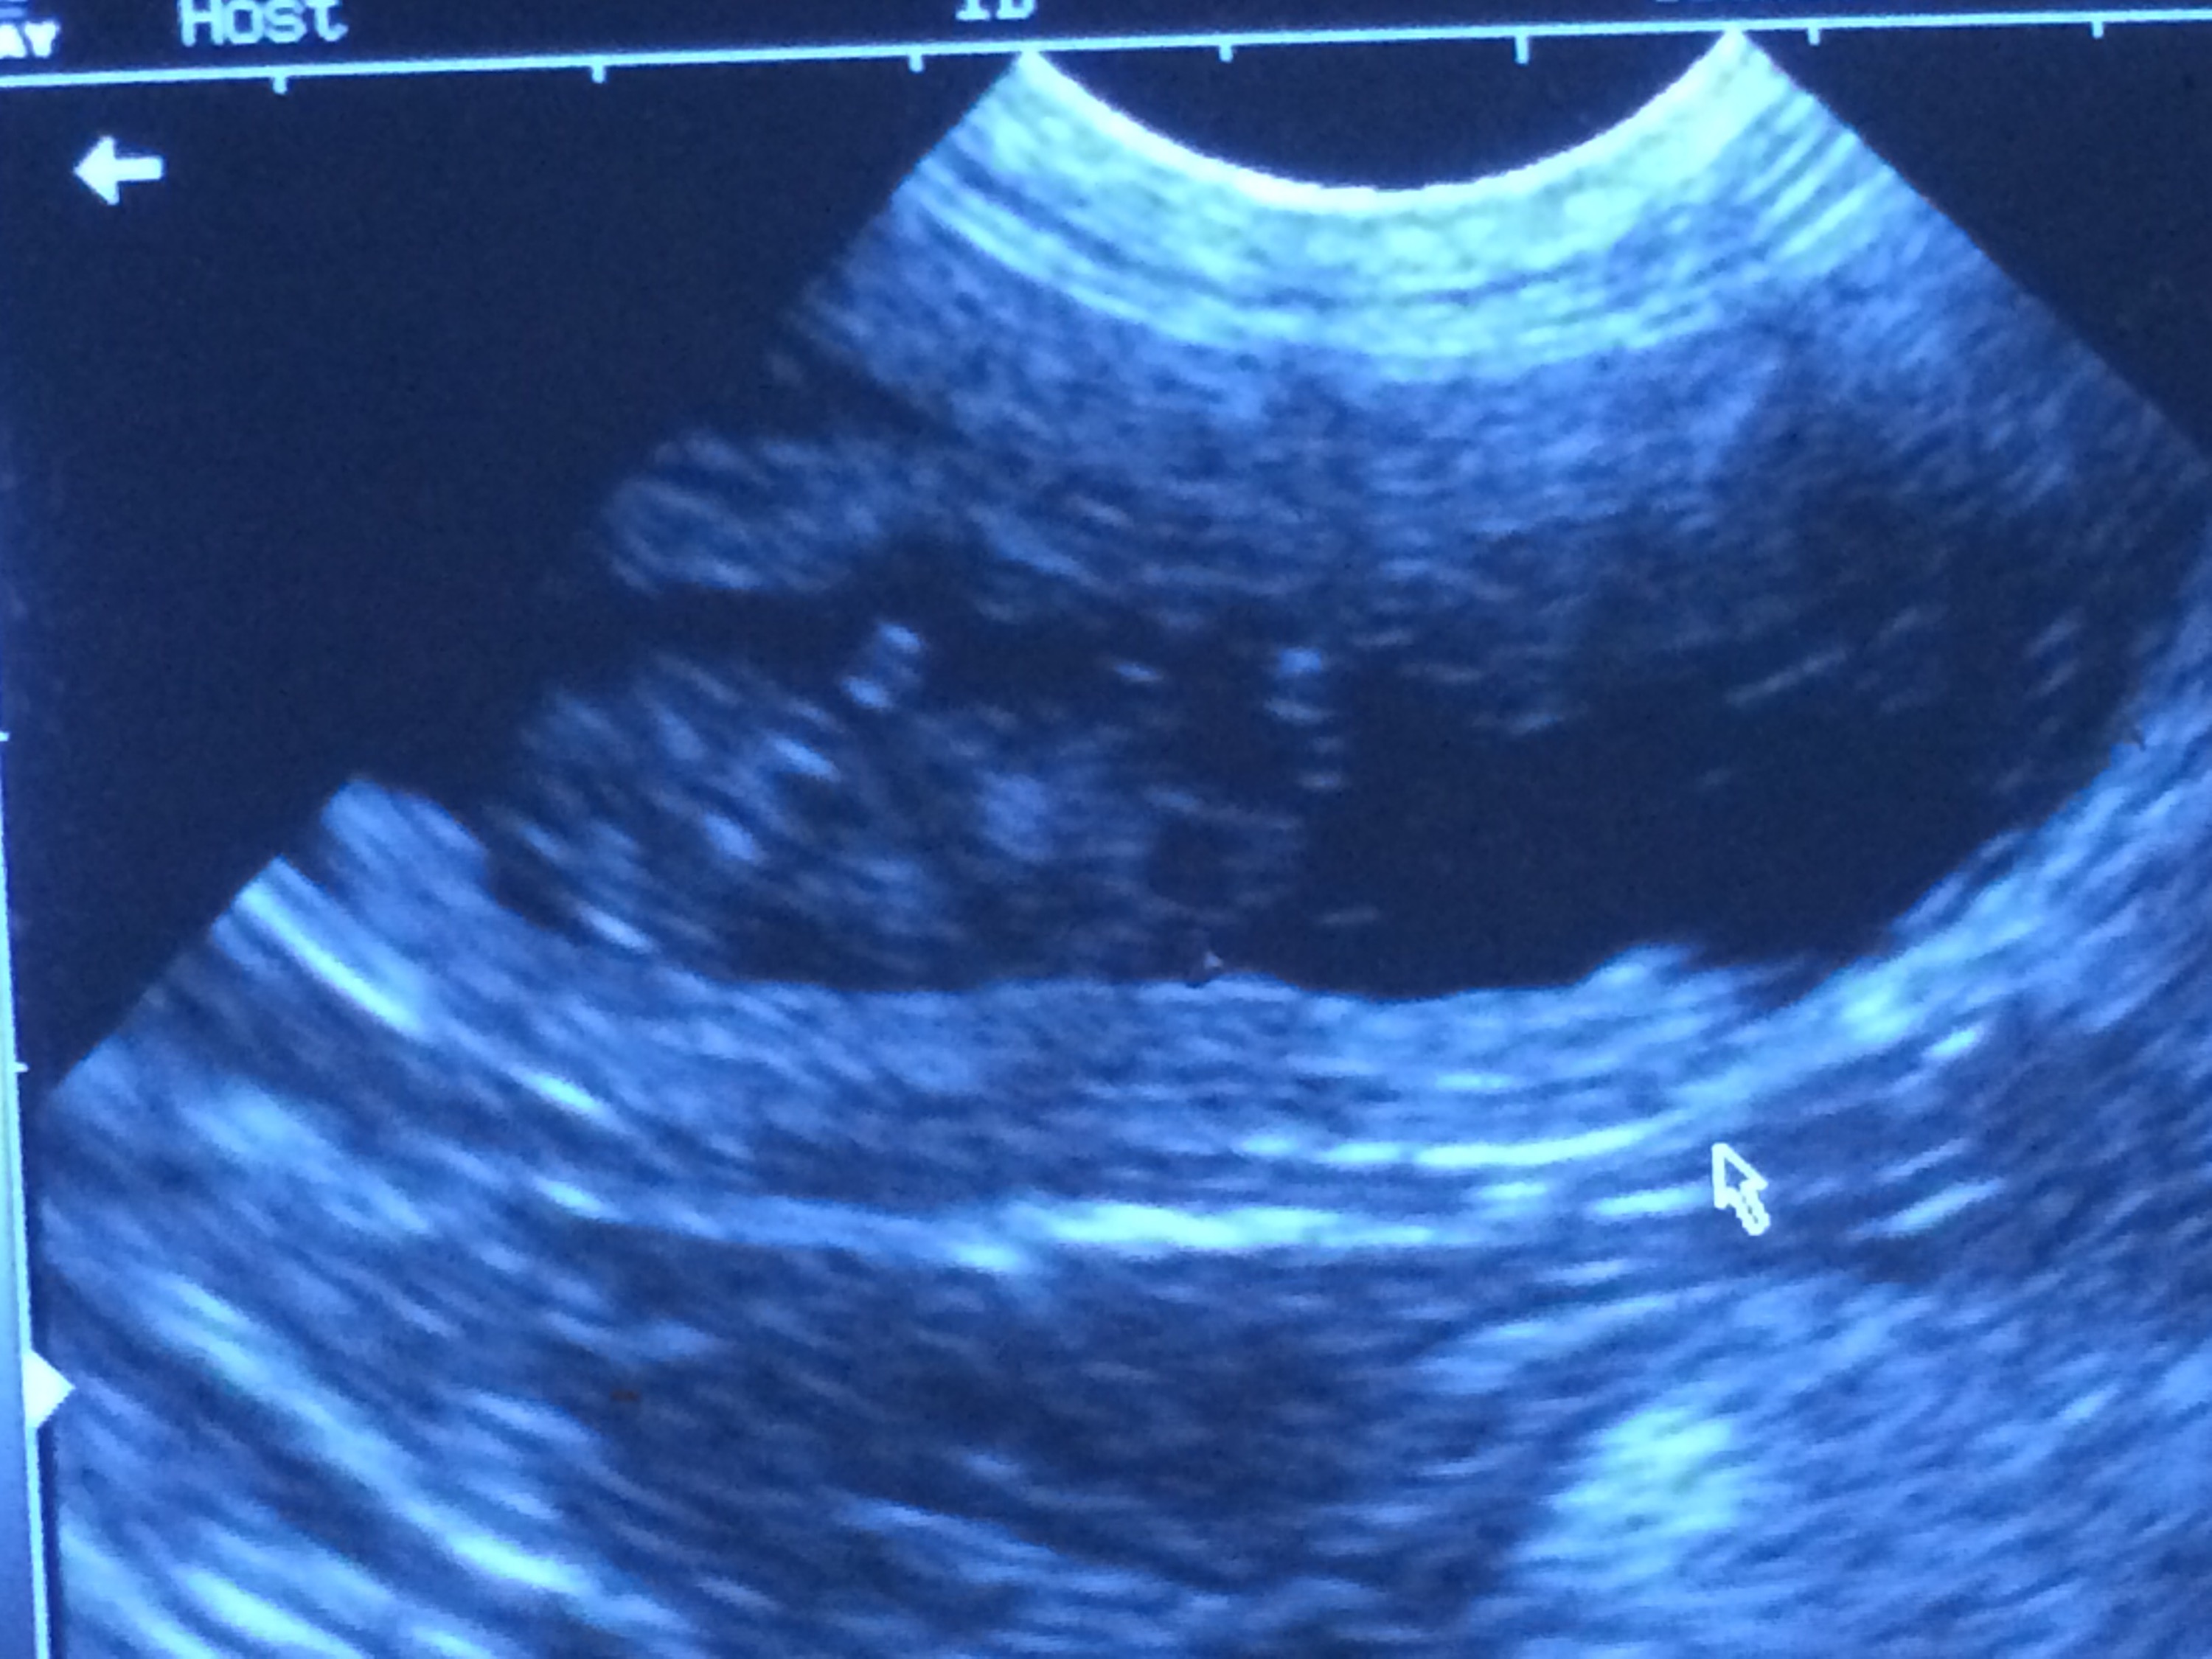

30 dagar har gått sedan parning och hon har gått upp 1 kg. Åkte in för att ultraljuda henne imorse för att se om där var några valpar. Men med de tecken jag har sett de senaste veckorna rådde det inga tvivel om att magen var full.

Vi fick se tre valpar på samma bild, det var en extremt häftig känsla. Fick även en bild på en valp med tassarna i luften.

Så nu är min magkänsla bekräftad. Valpar har hon. Sen hur många, det återstår att se. Med tanke på att de låg tätt så är där nog några stycken.